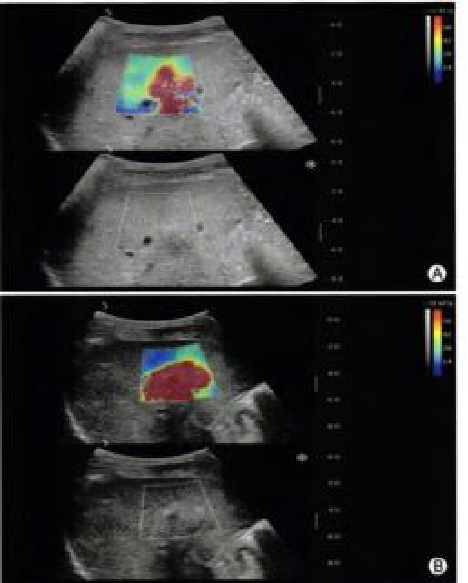

实时剪切波弹性成像

评估组织的软硬,并且提供定量数值,从而提示组织的良恶性。

image.png

鉴别诊断、精准分级、定量评价、穿刺引导、疗效评估、随访观察

恶性占位常常向周边组织进行侵润及扩散,二维很难观察到浸润部分的边界。使用实时剪切波成像能够对占位及周边组织进行硬度评估,通过颜色编码来区分不同组织的硬度信息,直观的观察占位组织的边界信息,更方便区分占位组织和正常组织的边界,准确评估消融范围。